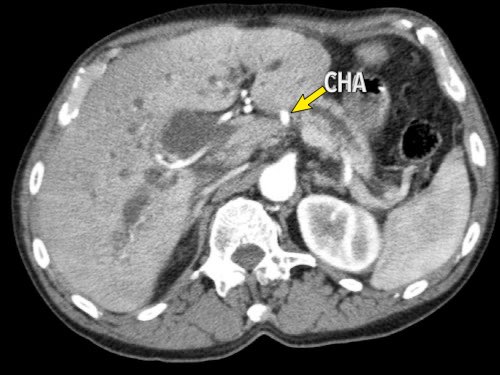

Tái tạo mặt phẳng coronal cho thấy một khối u lớn xuất phát từ cổ tụy với kiểu phát triển xâm lấn (hình A và B).

Có hiện tượng bao quanh động mạch thân tạng 360º (mũi tên trong A).

CT axial MIP tại mức động mạch thân tạng cho thấy hẹp động mạch gan chung bị bao quanh (mũi tên), rất nghi ngờ xâm lấn.